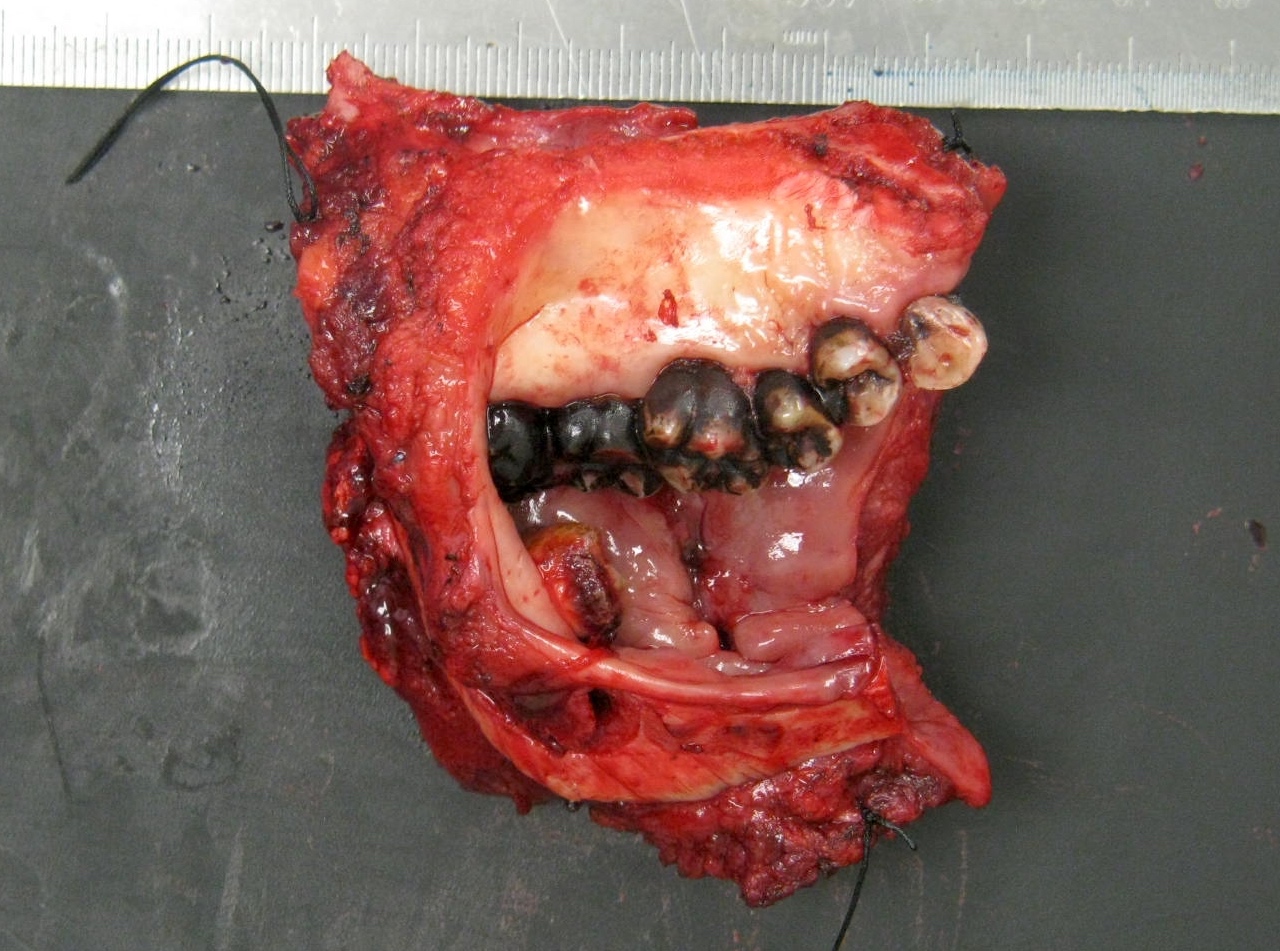

Gross description

- Macroscopic appearance varies with the morphologic type

- Common conventional squamous cell carcinoma shows an ulceroproliferative mucosal lesion with a firm gray-white infiltrative surface

- Verrucous and papillary squamous cell carcinomas demonstrate prominent exophytic, finger-like projections

- Spindle cell carcinoma generally presents as a mucosal polypoid lesion